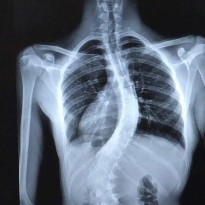

A pediatric checkup revealed what Alyssa couldn’t feel. She had adolescent idiopathic scoliosis (AIS), a curvature of the spine that was already at 36 degrees.

Latorree Garrett describes the first time she saw an X-ray of her daughter’s spine. “To me, it looked like a lizard,” she says. Despite the shock of seeing the severe curvature of her daughter’s spine, she was thankful to finally have a diagnosis for her daughter, now 2 ye...

Since he first began playing football at age 5, Treveon, now a high school sophomore, has dreamed of playing college ball, maybe even going pro. But in eighth grade, he was temporarily sidelined, when a routine visit to his pediatrician revealed a hump on his upper back. X-rays showed a curvature...

MaKayla’s scoliosis diagnosis came as a complete shock. The petite 13-year-old was a cheerleader, tumbled and played competition softball. By all appearances, she was perfectly healthy. Yet, in September 2015, a visit to a chiropractor for a back injury resulting from a trampoline incident ...